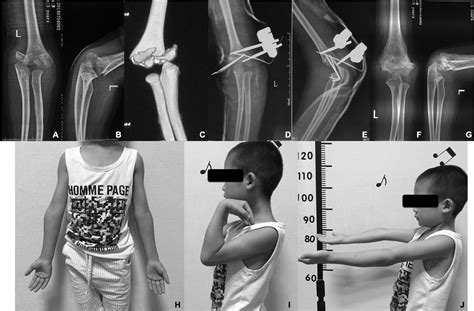

Surgical Treatment

For displaced or completely displaced fractures (Type II and Type III), surgical treatment is often required to realign the bone fragments and stabilize the fracture. Common surgical procedures include:

• Closed reduction and percutaneous pinning (CRPP): This procedure involves manipulating the bone fragments back into place without open surgery and then inserting pins to hold them in position.

• Open reduction and internal fixation (ORIF): In more severe cases, open surgery may be necessary to realign the bone fragments and secure them with plates, screws, or other hardware.

Surgical treatment aims to restore the normal anatomy of the elbow and promote healing. Post-operative care typically includes immobilization, pain management, and physical therapy to regain range of motion and strength.

While most supracondylar humerus fractures heal without complications, there are potential risks and complications to be aware of. These may include:

• Nerve injury: Damage to the nerves in the elbow area can lead to numbness, tingling, or weakness in the hand or fingers.

• Vascular injury: Injury to the blood vessels can result in reduced blood flow to the hand, leading to ischemia or compartment syndrome.

• Malunion or nonunion: Improper healing of the fracture can result in malunion (healing in a deformed position) or nonunion (failure to heal).

• Stiffness or loss of range of motion: Prolonged immobilization or inadequate rehabilitation can lead to stiffness and limited range of motion in the elbow.